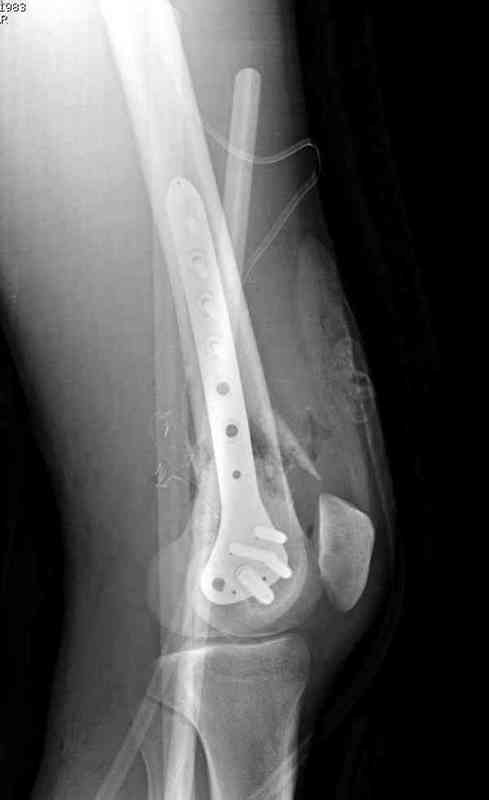

Пострадавшему 23, пистолетная огнестрельная не кроветочащая рана, меньше одного см диаметром, входное отверстие расположено латерально, и выход передне-медиально, и еще имеется второе пулевое ранение правой navicular bone с этой стороны.

Доступ был латеральный, при вскрытии с задней

поверхности бедра обнаружили кровотечение. Поднятием давления на заранее установленном турникете на конечности проконтролировали кровотечение.

В данном случае мы не ставили осуществление гемостаза приоритетным, после 30 минут больной оставлен вызванному сосудистому хирургу со стабильной фиксацией бедра. Несмотря на выбранный передне-медиальный доступ, хирург произвел восстановление сосудистого повреждения.

Латерально пластину защитили ушиванием

илио-тибиального тракта, а медиальная сторона была ушита мышцей, и все раны закрыли ваккумированием (VAC)

На третий день после Irrigation & Debridment закрыли все раны за исключением компартментальной раны из-за отека, медиально в дефект кости установили Putty Grafton Bone Substitute. На компартментальную рану вакуум и мероприятия по сближению краев раны резиновой стяжкой.

На 9й день с момента травмы ушили рану без натяжения. Больной получает реабилитацию, движения коленного сустава с помощи CPM-continuous passive motion machine. Сегодня выписан.